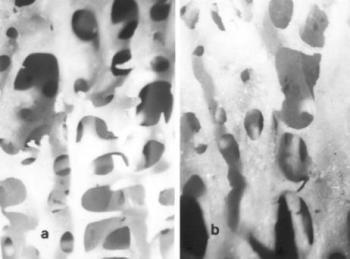

38. ábra. Az enthesopathias területen sűrű, vaskos csontgerendázat ábrázolódik. 20× nagyítás a) Ép íntapadási részlet trabeculái b) Az enthesopathiás területen vaskos, egy irányba rendezett gerendázat látható

43. ábra. a) Forestier-kóros csigolya-összenövések kizárólag az elülső régiót érintik, a kisízületek (nyíl) szabadok. 10–13. század, senilis korú férfi b) A csigolyatestek, a discusok nagy része és az intervertebralis kisízületek is összecsontosodnak (nyíl) Bechterew-kórban. 10–12. század, 30–40 éves férfi